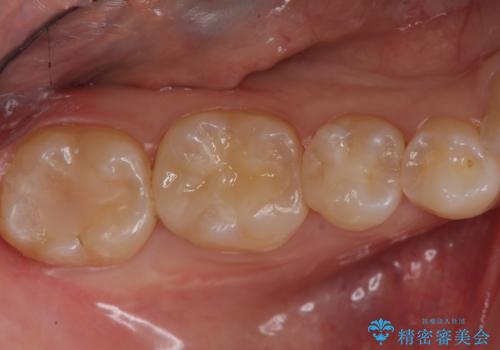

セラミック治療 → セラミックインレー

歯と歯の間によくものが詰まる。。セラミック治療

銀の詰め物を白い物にしたい